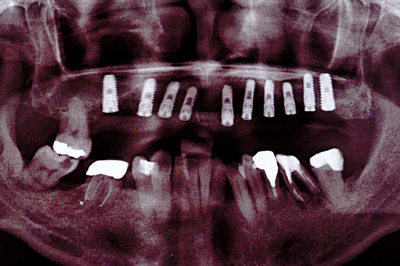

2診査

病歴や健康状態に関する問診、口の中の検査、レントゲン写真とCTや歯型の採取を行います。